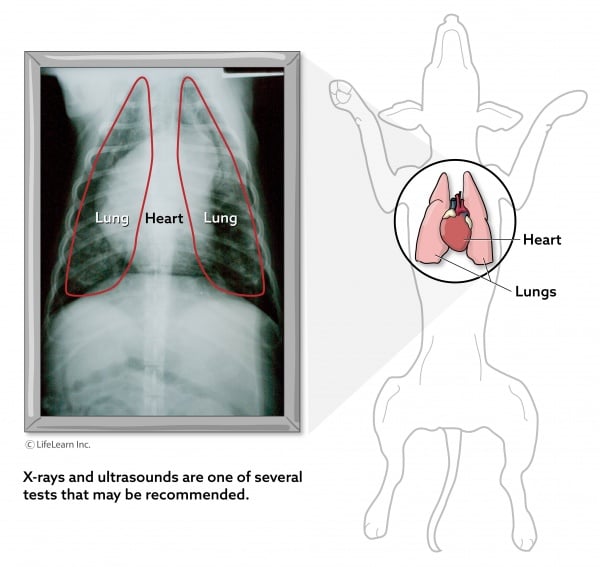

- Chest radiographs (X-rays). Dogs with pericardial effusion may have a characteristic appearance to the heart on radiographs, which can support the diagnosis. It is important to note, however, that a chest radiograph cannot definitively diagnose pericardial effusion and does not provide any information about how well the heart is functioning.

- An ultrasound of the heart can provide a definitive diagnosis of pericardial effusion, while also providing information on how effectively the heart is moving blood.